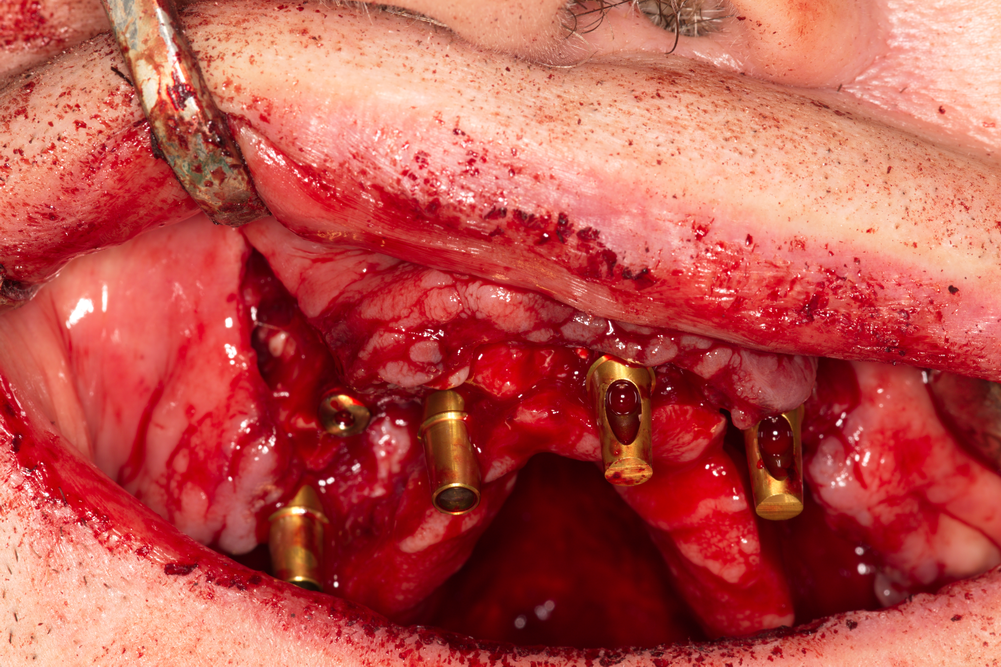

Снимка на поставянето на интраосален (вътрекостен) зъбен имплант. В огромен процент от случаите (над 99 % в световен мащаб) в съвременната имплантология се използват именно вътрекостните импланти - интраосален всъщност означава вътрекостен. В миналото е имало опити за поставяне и на други видове импланти - трансосални и субпериостални, но с течение на времето като истински надеждно и трайно лечебно средство се е доказал класическият вътрекостен имплант - независимо дали е двучастов или едночастов. Към момента няма информация за приложението на трансосални импланти някъде по света; субпериостални импланти обаче се прилагат в ограничени случаи на силно изразена атрофия - предимно на долна челюст. Освен това съществуват и субмукозни и трансосални импланти; те обаче се поставят изключително рядко. Първият тип импланти се поставя само под лигавицата и поради това механичната им задръжка не е надеждна; вторият тип пробожда костта в пълна дебелина, което прави имплантацията изключително травматична, а оздравителният процес - бавен и не особено приятен. Поради това трансосалните импланти намират приложение предимно в областта на ортопедията и травматологията - като средство за фиксация на фрактурирани кости, за костни дистракции, за корекция на различни вродени малформации и много други.

Поставени интраосални импланти от системата TBR - Франция. Нашият екип е привърженик на поставянето на по възможност по-голям брой импланти - навсякъде, където това е възможно. Предимствата на подобен лечебен подход са безспорни - намалява се механичното претоварване, елиминират се мостовите тела (под които се задържа зъбна плака), намалява се честотата на протетичните усложнения и като цяло постигнатият резултат е по-траен и по-стабилен с течение на времето. Вижда се циркониевият пръстен в областта на имплантатната шийка. Той служи за адаптация на меките тъкани и при добро планиране и изпълнение на клиничния случай е възможно да се получат наистина впечатляващи естетични резултати. Проблем представлява голямата височина на имплантатната шийка - понякога около нея се формира постоперативен хематом и това удължава заздравителния процес. Това обаче се случва единствено при опит за покриване на циркониевия пръстен и надлежащия винт с лигавица и периост - тогава субмукозно остава значително по обем празно пространство, което се изпълва с кръв. Имплантите на системата TBR са от типа tissue level, а не bone level - т.е. имплантатната шийка при тях трябва да се разположи на нивото на меките тъкани, а не под нивото на костта. Всичко това изисква запознаване на хирургичния протокол в детайли и стриктно спазване на всички предписания и концепции на производителя - тъй като те са отдавна изпитани във времето и освен това са обект на непрекъснати клинични проучвания и усъвършенстване. Нашият екип винаги се опитва да прави съответните аналогии с цел по-добра визуализация на описаната материя. В този случай се прилага една сентенция от областта на авиацията - всичко, което знаем от практическа гледна точка, е писано с много кръв; в областта на хирургията и медицината като цяло това твърдение е валидно с особено голяма сила.